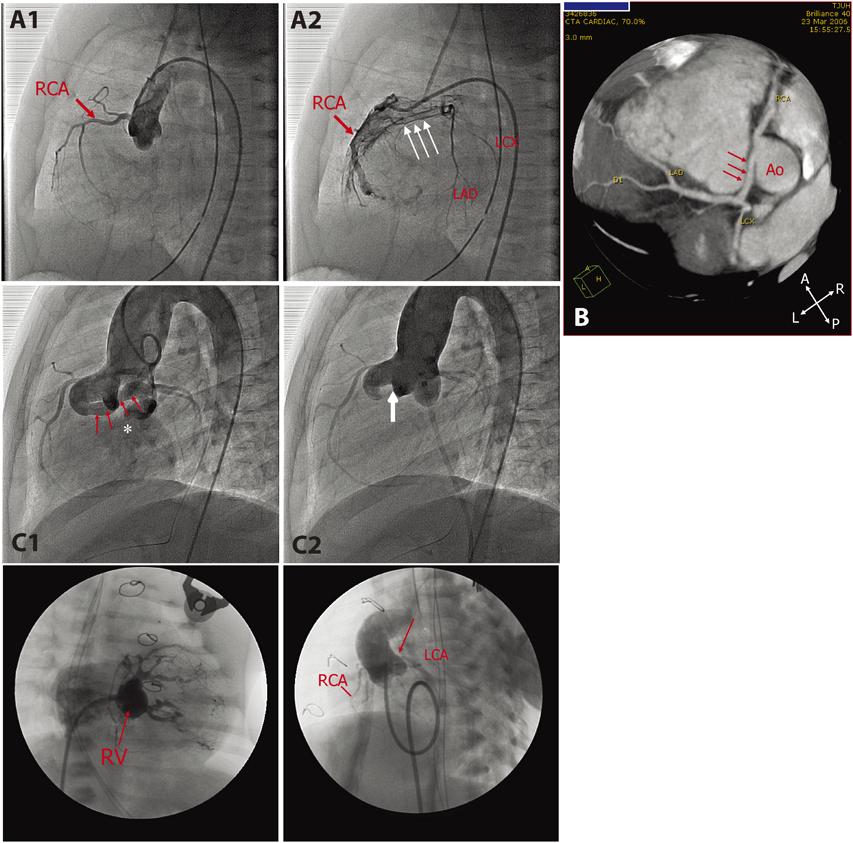

Fig. 2 Acquired coronary anomalies in children. A1 and A2: Selective coronary angiograms of a 9-year-old girl with Kawasaki disease who developed a giant aneurysm during the acute phase (A1: RCA and A2: LCA). B1 and B2: Aortic root injection an 8-year-old girl with d-TGA who underwent aortic switch operation in the newborn period who developed sudden cardiac arrest during exercise. She had been totally asymptomatic until this near-lethal event. Filling of LCA was delayed by a few seconds with severe ostial stenosis. No collateral vessel formation was noted. C1 and C2: Coronary angiograms of a 12-year-old girl who underwent orthotopic heart transplant for dilated cardiomyopathy at 10 years of age. C1: Aortic root injection showed normal-sized LCA and diffusely hypoplastic RCA (C1), which was confirmed by selective RCA angiogram (C2)

Kawasaki disease is known to cause coronary artery deformation, ectasia, and/or aneurismal formation during and after the acute phase of the disease.48, 49) Coronary aneurysm and secondary coronary stenosis as the results of uneven regression of ectasia are thought to predispose to vascular occlusion (Fig. 2A1, A2). Aneurysms are mainly seen at the proximal coronary arteries or at the bifurcations. Echocardiogram is useful in detecting these coronary lesions that evolve dynamically over time.50) Aneurysm may increase in size over the first 2 months, depending upon the degree of vasculitis, followed by spontaneous regression by 2 years after the onset; however, vascular stenosis progresses over many years.50, 51) Due to the early introduction of high-dose intravenous immunoglobulin (IVIG), the incidence of coronary aneurysm and its complications are dramatically decreased.52, 53) Vascular occlusion by thrombus formation and/or intimal thickening results in myocardial ischemia, infarction, or sudden cardiac death.54) Of 60 patients who developed myocardial infarction following Kawasaki disease, 50% developed within 6 months after the onset. Fifteen patients (25%) died, 3 died during the acute phase, and 12 patients died during the chronic phase. Half of the late deaths (6 patients) were of sudden unexpected death.54) The late sudden cardiac death frequently occurs in asymptomatic patients.55)

d-Transposition of the Great Arteries after Arterial Switch Operation

Arterial switch operation (ASO) is primarily indicated in the newborn period for surgical repair of d-loop transposition of the great arteries (d-TGA) and Taussig-Bing anomaly. Because the procedure involves translocation of the coronary arteries, coronary complications may occur during the acute56, 57) and chronic phases.58–60) While short-term coronary complications are related to intrinsic coronary artery anatomy and surgical procedure per se, long-term complications frequently occur unexpectedly without any associated clinical signs or symptoms58, 61, 62) (Fig. 2B1, B2). Routine ECG, echocardiogram, exercise stress test (EST), and myocardial perfusion imaging (MPI) are neither sensitive nor specific to identify most of preclinical coronary disease.58, 63) Affected patients are usually asymptomatic or unexpectedly present with lethal (sudden death) or near-lethal (ventricular fibrillation) events. Pathological specimens reveal an intimal thickening of obliterated coronary arteries,60, 64) but the underlying mechanism of this process remains largely unknown. The necessity of routine coronary imaging study in post-ASO patients is advocated by certain groups, including the current author, to risk-stratify a preclinical coronary disease after ASO.60, 65, 66)

Cardiac Allograft Vasculopathy

Cardiac allograft vasculopathy (CAV), a diffuse coronary narrowing known to occur in the recipients of heart transplant, is a major risk factor in limiting long-term survival after heart transplantation.67–69) Unlike atherosclerotic coronary disease, CAV causes diffuse narrowing of coronary arteries (Fig. 2C). Histopathologically, CAV is characterized by the proliferation of vascular smooth muscle cells in the allograft and concentric intimal thickening.70) The pathogenesis of diffuse intimal thickening associated is thought to be due to multiple factors including chronic rejection, endothelial dysfunction, infection, and traditional cardiac risk factors (hypertension, hypercholesterolemia, and diabetes mellitus),67, 71) but the precise mechanism is not fully understood. The incidence of CAV in children is less than that in adults, but is known to occur in 5% to 7% within 2 years after transplant and 15% to 18% within 5 years after transplant.72) The prognosis of CAV is poor, as approximately 50% of cases will result in either graft loss or death within 2 years after the diagnosis.72, 73) Clinical presentation is variable and frequently nonspecific, as the affected patients may not complain of typical anginal pain because renervation over the implanted heart is often incomplete.74) The presence of abdominal, chest, and/or arm pain after heart transplant, however, is strongly associated with CAV and sudden death or aborted sudden death.75) The effective treatment or prevention for CAV is currently not known, but new data are emerging that can potentially help control or attenuate the development of pathological vascular remodeling.76)